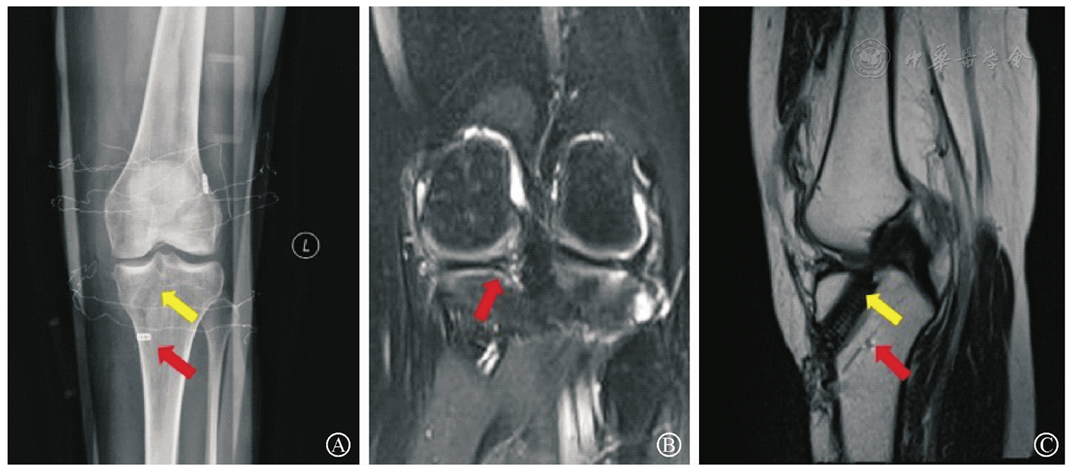

图6 经胫骨隧道拉出悬吊技术修复MMPHRT(内侧半月板后根部撕脱)+ACL(前交叉韧带)重建术后影像。图中红箭头示半月板胫骨隧道位置,黄箭头示ACL重建后胫骨隧道位置。图A为术后膝关节正位X线片;图B为术后1年膝关节冠状位MRI,示MMPHR愈合,半月板信号连续,未见T2信号;图C为术后1年膝关节矢状位MRI,示半月板胫骨隧道内口位于内侧半月板根部,骨隧道愈合,黄箭头示ACL重建后胫骨隧道位置良好,未见骨隧道扩大